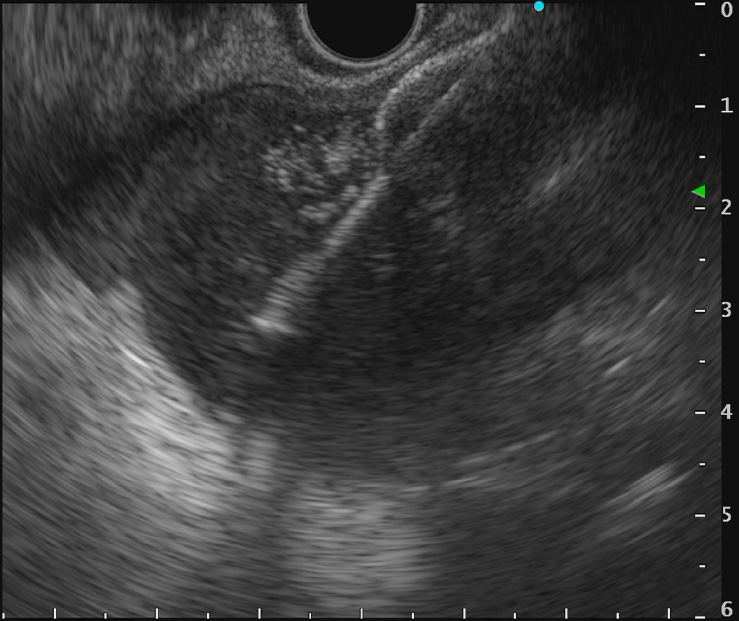

重症急性膵炎後のWONに対するEUS下膿瘍ドレナージ